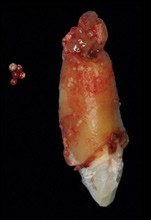

8. Tooth No. 8 with diagnosis of Grade III socket, requiring extraction followed by guided bone regeneration and a rotated pedicle flap to gain hard and soft tissue for future implant placement.

Figure 8

9. Tooth No. 8 with diagnosis of Grade III socket, requiring extraction followed by guided bone regeneration and a rotated pedicle flap to gain hard and soft tissue for future implant placement.

Figure 9

10. Tooth No. 8 with diagnosis of Grade III socket, requiring extraction followed by guided bone regeneration and a rotated pedicle flap to gain hard and soft tissue for future implant placement.

Figure 10

11. Tooth No. 8 with diagnosis of Grade III socket, requiring extraction followed by guided bone regeneration and a rotated pedicle flap to gain hard and soft tissue for future implant placement.

Figure 11

Based on the single extraction socket roadmap developed by El Chaar and colleagues, the socket of tooth No. 8 was diagnosed as Grade III and would require initial treatment that included the extraction of failing tooth No. 8 followed by simultaneous guided bone regeneration and soft-tissue augmentation by means of a rotated palatal pedicle flap (Figure 8 through Figure 11).27,28 The principles of and guidelines for both the ridge augmentation and rotated pedicle flap have been described in the literature and will not be focused on in this case report.27-30 The patient was temporized with a bonded Maryland bridge that was adjusted to avoid creating pressure on the tissue during healing (Figure 12).